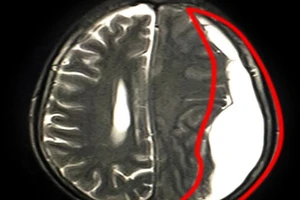

Suýt mất mạng do máu tụ dưới màng cứng mạn tính